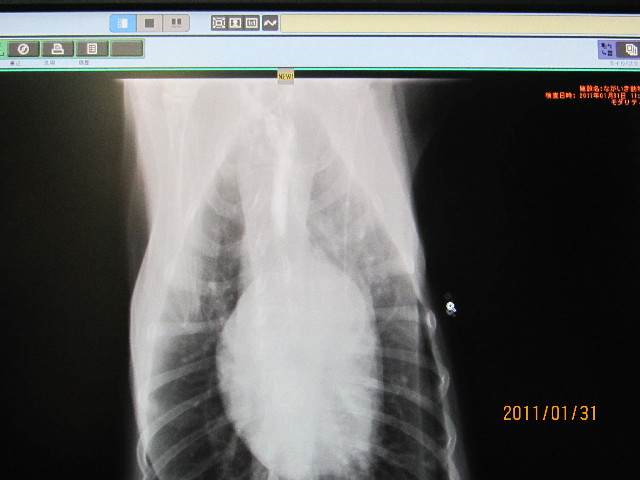

レントゲンでみると胃につながる少し前のこのへんです。

横隔膜のところなので見にくいですが、先生方はちゃんと異変に気付いて下さっていたのです。